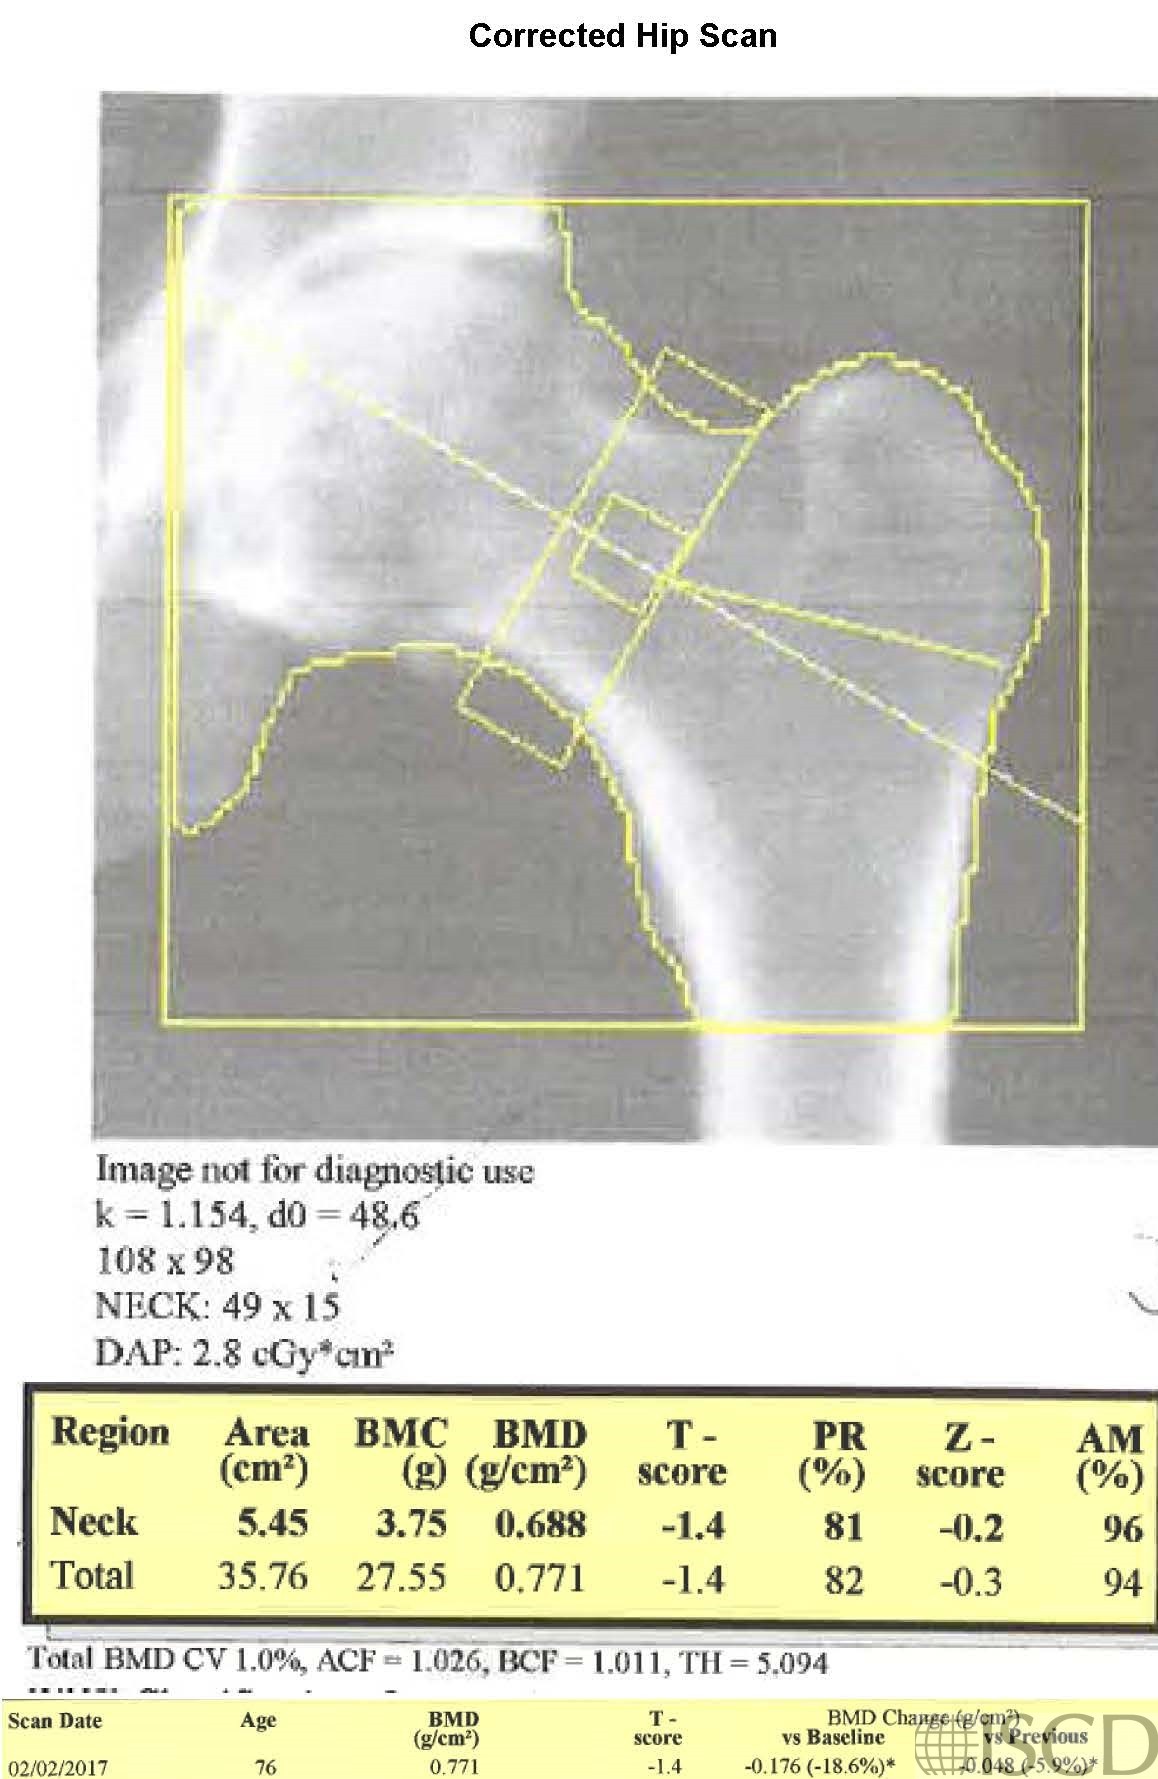

This panel shows the corrected follow-up scan, where the hip global region of interest size is now the same as baseline. Using the 95% confidence interval for the institution at the total hip, there is now a significant loss of bone density, using the 95% confidence intervals of the institution.

The upper left panel shows the baseline scan. The size of the global region of interest box is 108 x 98 pixels. The upper right image shows the follow-up scan, where the size of the follow-up global region of interest is 106 x 99 pixels, which is not the same as the baseline scan. The bottom image shows the corrected scan, where the global region of interest is the same size. In this case, with the incorrect size, there was not a significant change in hip bone mineral density. With the corrected scan, there is now a significant decrease, using the institution 95% confidence interval for the total hip